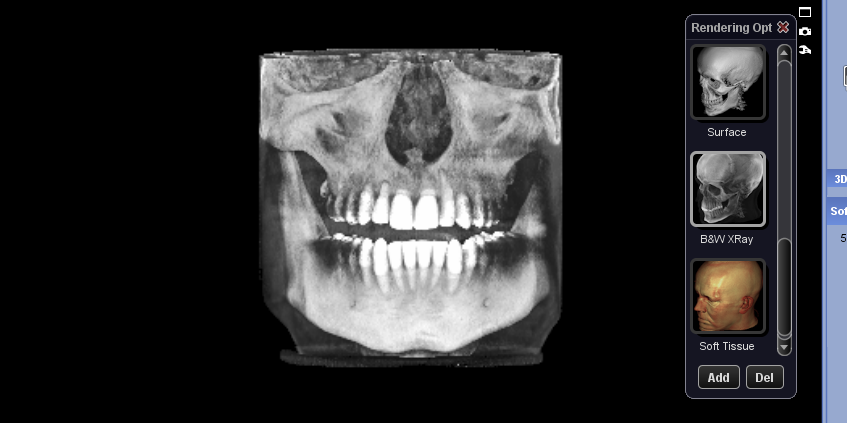

How long does swelling from lefort 1 Downgrafting (no advancements) last? And how does it affect nose size?

I’ve heard nose can get permanently wider after lefort 1 my nose is already very wide and i dont want to get rhino later

I’ve heard nose can get permanently wider after lefort 1 my nose is already very wide and i dont want to get rhino later